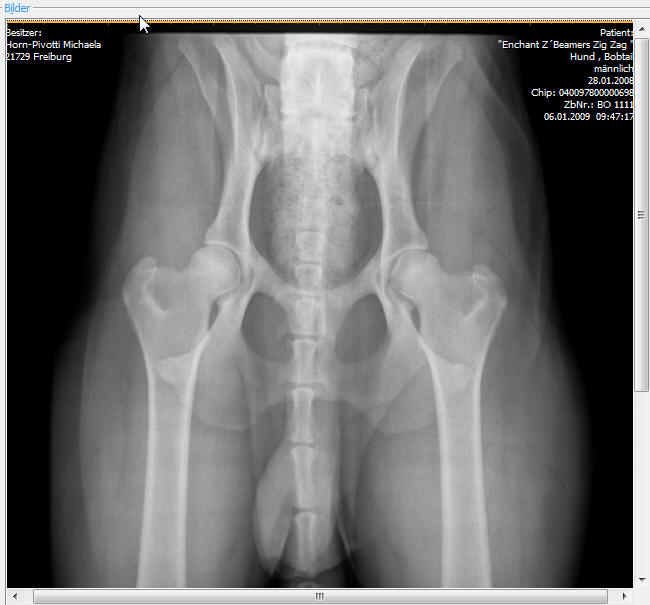

und Zag wird mit diesem Gebiß jetzt lebenslang weiterhin ungehindert jeden Knochen zerlegen können. Er ist HD und ED frei - hier das Bild seiner Hüfte: